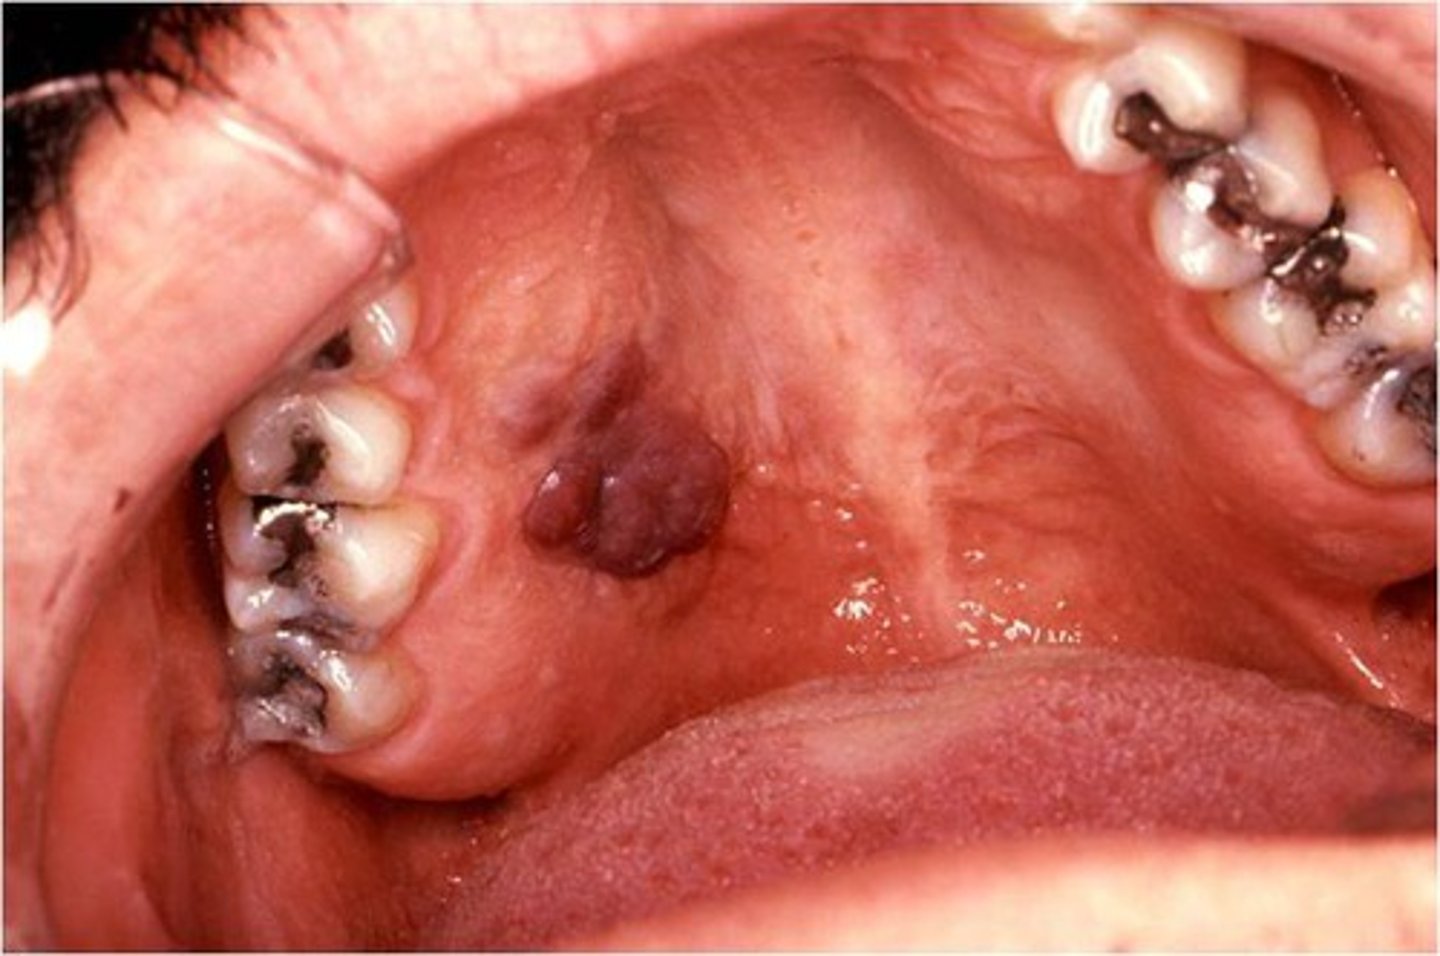

Name the pathology: oral manfestation in aids patients. a malginant cnacer of the lining of blood vesels on the ______. May present as purple lesionson the palte. TX: ?

kaposi sarcoma

hard palate

tx: provide normal dntal treatment but NO invasive treatment